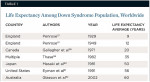

Trisomy of the 21st chromosome is present with phenotypic expression in 95% of patients with Down syndrome, or trisomy 21 (T21).1,2 The remaining cases are attributed to other chromosomal abnormalities, including translocation (3%), mosaicism (2%), and partial trisomy.2 The phenomenon occurs during spermatogenesis or oogenesis, resulting in a chromosome that has three copies. The incidence of T21 is one in 800 to 1,000 live births in the United States.1 Worldwide, life expectancy among this population is increasing (Table 1). The disorder has immunologic and physiologic differences that contribute to these patients’ poor periodontal condition.